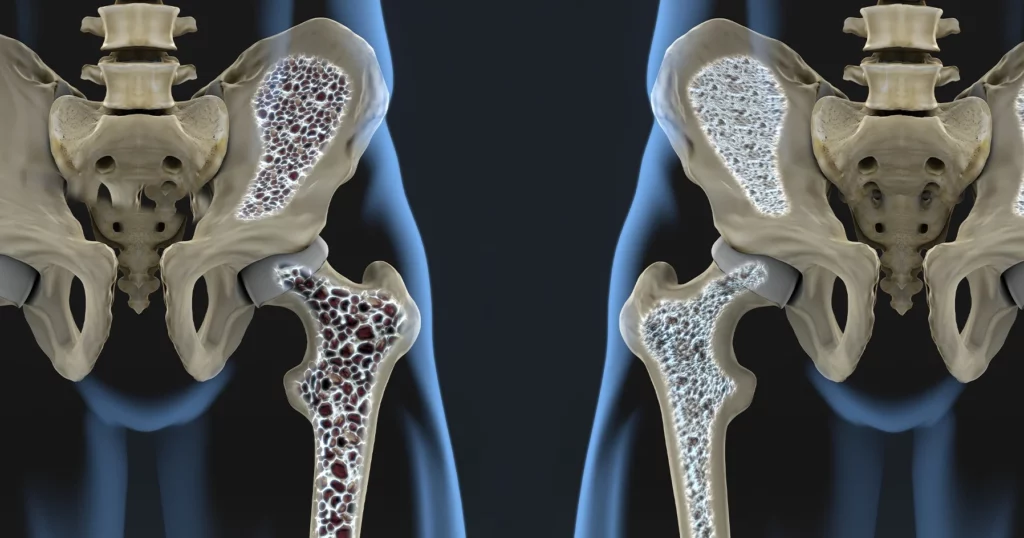

O descoperire revoluționară în domeniul medicinei ar putea schimba felul în care tratăm osteoporoza. O echipă de cercetători din Germania a identificat un receptor din organism care pare să joace un rol crucial în rezistența osoasă. Activarea acestuia, în cadrul unor experimente pe animale, a condus la creșterea densității osoase și la regenerarea țesutului deteriorat.

Osteoporoza, o boală care afectează milioane de oameni la nivel mondial, slăbește oasele, crescând riscul de fracturi. Noile cercetări, efectuate la Universität Leipzig, oferă speranțe pentru dezvoltarea unor tratamente mai eficiente și mai specifice. Receptorul GPR133, până acum relativ necunoscut, pare să fie o țintă promițătoare pentru intervenții terapeutice.

Cercetătorii au descoperit că GPR133 controlează direct rezistența oaselor. Prin activarea acestui receptor, s-a reușit stimularea formării de țesut osos nou și repararea celui afectat de osteoporoză. Experimentele, realizate pe animale, au demonstrat eficacitatea acestei abordări. Rezultatele sugerează că activarea GPR133 ar putea reprezenta o strategie eficientă pentru combaterea osteoporozei.